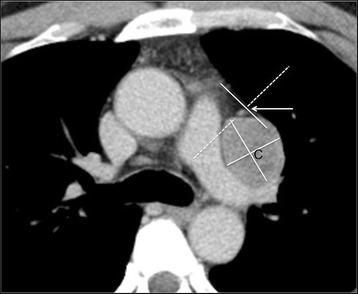

Identification of the pericardiacophrenic vein on CT.

To evaluate the depictability of pericardiacophrenic veins (PCPV) as landmarks for the location of the phrenic nerves on multi-detector-row computed tomography (MDCT), and to investigate the usefulness of depicting the PCPV to aid differential diagnosis of anterior mediastinal lesions.

Fifty-six patients with anterior mediastinal lesions (Fifty lesions originated from the thymus, six were of non-thymic origin) were evaluated. Contrast-enhanced CT scans of the chest were performed in all cases before diagnosis, and 22 of these scans were performed with electrocardiographic (ECG) gating. Two chest radiologists assessed the depictability of the PCPV and the positional relationship between the center of each anterior mediastinal lesion and the ipsilateral PCPV.

The use of ECG gating increased the PCPV depiction rate in the lower left part of the mediastinum. The depiction rate of the left PCPV was significantly higher than that of the right PCPV. All 50 tumors of thymic origin and 3 of the 6 tumors of non-thymic origin were located on the medial side of the ipsilateral PCPV. The 3 lesions located on the lateral side of the ipsilateral PCPV were of non-thymic origin (p = 0.0007).

The use of ECG gating during MDCT may improve the depictability of the PCPV in the lower left section of the anterior mediastinum. Solitary anterior mediastinal lesions located on the lateral side of the ipsilateral PCPV are likely to be of non-thymic origin.